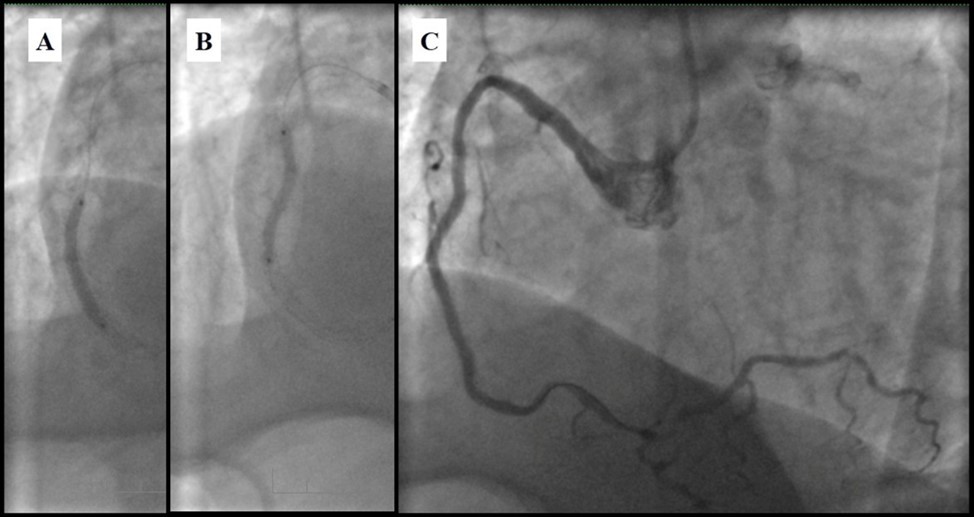

In the first stage, despite the fact that BMS is contraindicated in diabetic patients, RCA was stented with 3 bare-metal stents (BMS) (Rebel, Boston Scientific) (due to financial problems - drug-eluting stents was not covered by insurance). We used BMS to have at least temporarily patent RCA during LMCA stenting (Figure 5) (we believe that, when RCA is functional, LMCA stenting is safer). LAD was stented with 2 drug-eluting stents (Resolute Integrity, Medtronic). After the first PCI patient’s symptoms were relieved (Figure 6).

Figure 5.A, B, C - Stenting of the RCA with BMS; D - Angiography result.

Figure 6.A, B - Stenting of the LAD with DES; C - Angiography result.